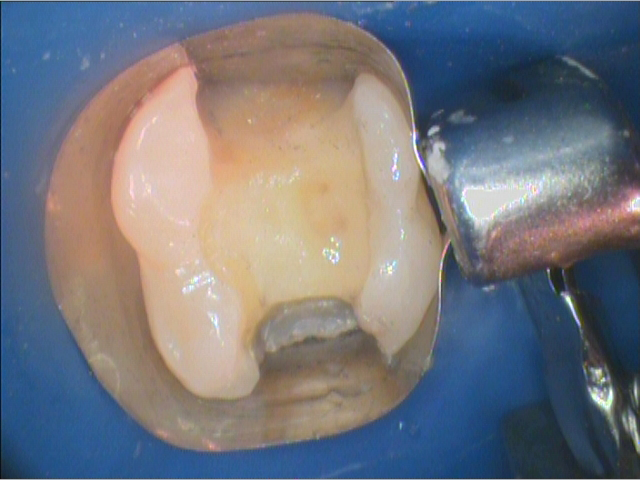

The patient was anesthetized with an inferior alveolar block with 4% Septocaine(1:100,000epi). Isolation was obtained with a rubber dam. The remaining amalgam restoration was removed with a high-speed carbide bur. The deep distal caries were excavated completely with a #6 round carbide bur with low torque. A very thin layer of dentin was left remaining over the pulp (Fig. 2). A traditional matrix band was placed. Biodentine was prepared, triturated and placed in a layer over the thin dentin (Fig. 3). The Biodentine was allowed to set for its 12-minute set time.The preparation was then refined and cleaned.

Fig. 3 Fig. 4